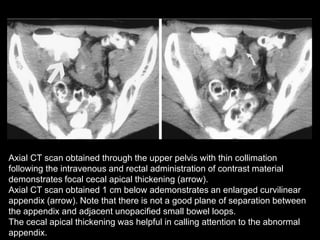

Axial CT scan obtained through the upper pelvis with thin collimation

following the intravenous and rectal administration of contrast material

demonstrates a normal-appearing proximal appendix originating from the

cecal apex (arrow).

demonstrates focal cecal apical thickening (arrow).

Axial CT scan obtained 1 cm below ademonstrates an enlarged curvilinear

appendix (arrow). Note that there is not a good plane of separation between

the appendix and adjacent unopacified small bowel loops.

The cecal apical thickening was helpful in calling attention to the abnormal

appendix.

Axial CT scanobtained through the upper pelvis with thin collimation following the intravenous and rectal administration of contrast material demonstrates a normal-appearing proximal appendix originating from the cecal apex (arrow).

Axial CT scanobtained through the upper pelvis with thin collimation following the intravenous and rectal administration of contrast material demonstrates focal cecal apical thickening (arrow). Axial CT scan obtained 1 cm below ademonstrates an enlarged curvilinear appendix (arrow). Note that there is not a good plane of separation between the appendix and adjacent unopacified small bowel loops. The cecal apical thickening was helpful in calling attention to the abnormal appendix.